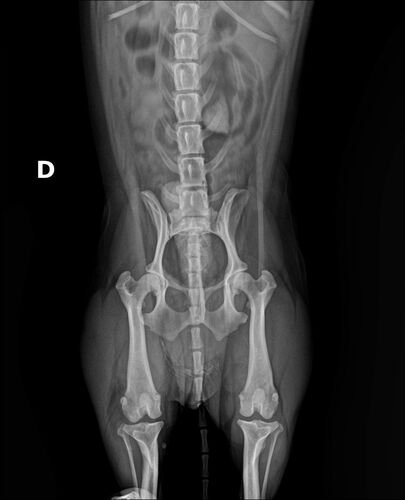

Oi aumigos, meu nome é Lord, tenho 9 anos e sou o amor da vida das minhas mães e a alegria de todos que convivem comigo. Fui atropelado e fraturei o final da minha coluna (vértebras sacrais), prejudicando minha patinha e meu rabinho, estou ver tudo

Oi aumigos, meu nome é Lord, tenho 9 anos e sou o amor da vida das minhas mães e a alegria de todos que convivem comigo. Fui atropelado e fraturei o final da minha coluna (vértebras sacrais), prejudicando minha patinha e meu rabinho, estou sentindo muita dor e preciso de cirurgia o mais rápido possível 😢. Como foi um acidente, pegou minhas mamães desprevenidas, peço ajuda de vocês, para que eu possa ficar curado e voltar a correr e brincar 🐶